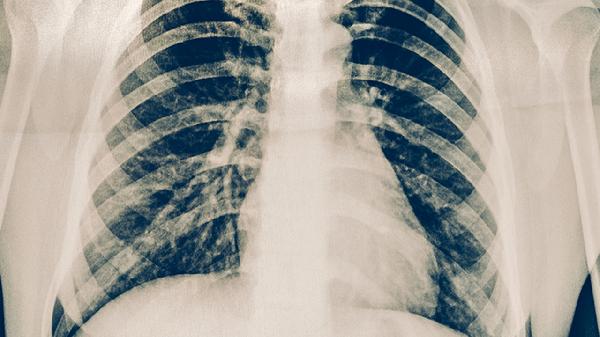

肋骨骨折患者除药物镇痛外,需保持患侧制动,避免剧烈咳嗽或深呼吸加重损伤。恢复期可适量补充富含钙质和维生素D的食物如牛奶、鱼类,促进骨骼愈合。疼痛持续不缓解或出现呼吸困难、发热等症状时,应立即复诊排除并发症。所有药物均须在医生指导下使用,不可自行调整剂量或联合用药。